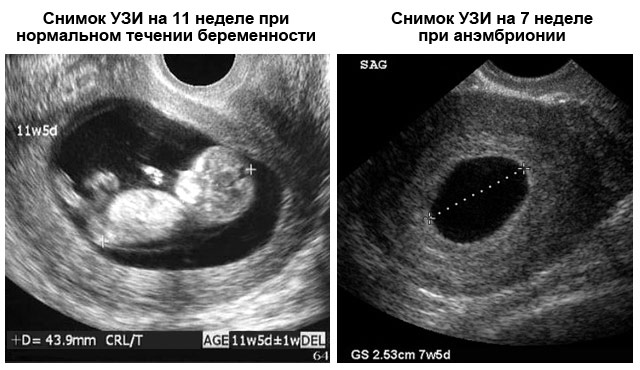

Если во время трансабдоминального УЗИ на шестой неделе беременности врач не обнаруживает сердцебиение, но видит плодное яйцо и эмбрион, обследование может быть перенесено на 1-2 недели. Это связано с тем, что точно определить день зачатия бывает сложно, особенно при нерегулярном менструальном цикле, что может привести к ошибкам в расчетах срока. На повторном УЗИ сердцебиение, как правило, уже фиксируется. Если же его нет, это может указывать на замершую беременность.

Если УЗИ-специалист не находит биение сердца и не видит эмбриона, это может свидетельствовать о так называемой анэмбрионии – отсутствии эмбриона в плодном яйце. В таком случае для подтверждения диагноза назначается повторное обследование через 1-2 недели. Если результаты остаются прежними, диагноз подтверждается.